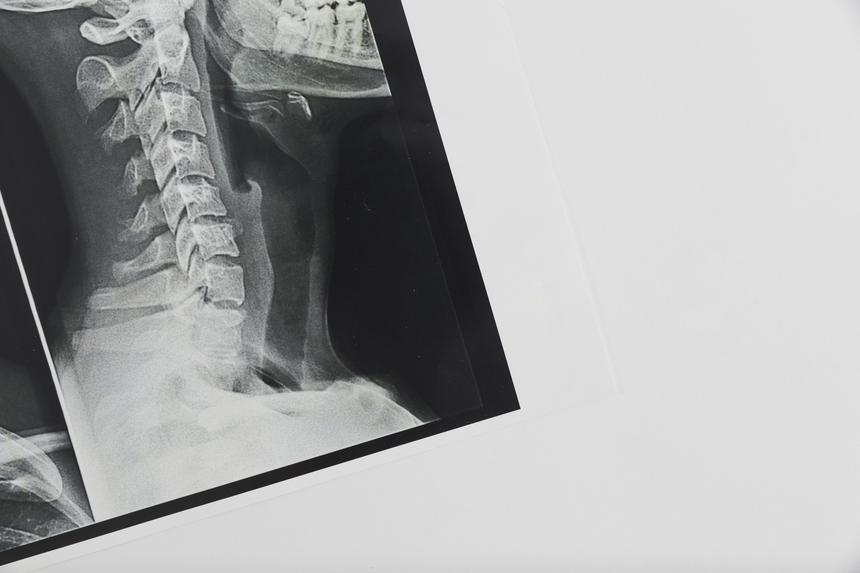

По данным источника, 64-летний мужчина неудачно упал на голову, после чего у него онемели руки и ноги. В критическом состоянии его госпитализировали, и уже в клинике врачи обнаружили у него оскольчатый перелом шейного позвонка со смещением и сдавлением спинного мозга. Такую травму называют «переломом висельника» и, по словам врачей, она часто смертельна. Однако россиянину повезло.

Пострадавшего экстренно направили на операцию, во время которой ему поставили на место смещенные позвонки и закрепили их винтами. Хирургическое вмешательство помогло сохранить двигательные функции.